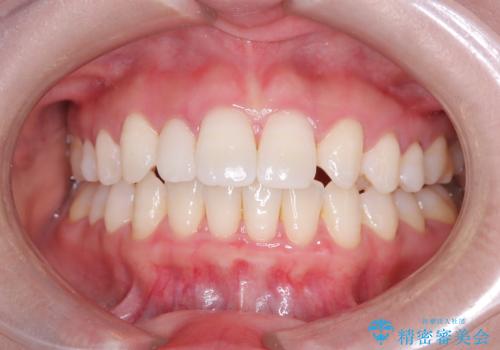

- 歯のデコボコと右上2番の歯の形が気になることを主訴に来院された患者様です。

軽度の叢生(凸凹)であったため、インビザラインのライトパッケージを用いて歯並びを改善しました。その後、右上2番はオールセラミッククラウンにより形態を回復し、審美性を向上させました。

歯並びと見た目がきれいになり、治療も短期間で終わったことから、患者様にも大変ご満足いただきました。